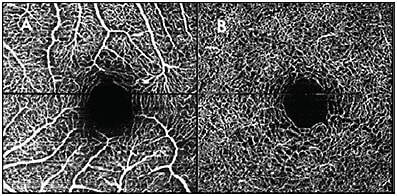

Analysis and interpretation of OCTA images can often be quickly accomplished by looking at the images of the en face vascular layers that have been automatically segmented and processed by the OCTA software (Figure 4). In healthy adult eyes, for which most of the image processing software has been written and trained to analyze, such a method of reading is sufficient. However, for eyes with pathological findings, manual segmentation and critical analysis of OCTA data may be required. The following are some tips on analysis of OCTA images.

Tip #1: Slice It and Dice It Yourself

As mentioned above, segmentation artifacts occur when the retinal layers are not identified correctly; this tends to happen when there is retinal pathology that deviates from the usual structure of the healthy adult retina. If blood vessels appear to stop abruptly and then reappear on a different OCTA layer, maintain a high degree of suspicion for errors in segmentation and manually review the segmentation of the B-scans through that area. Manually resegment the retina in at least a few B-scans through the problematic area.